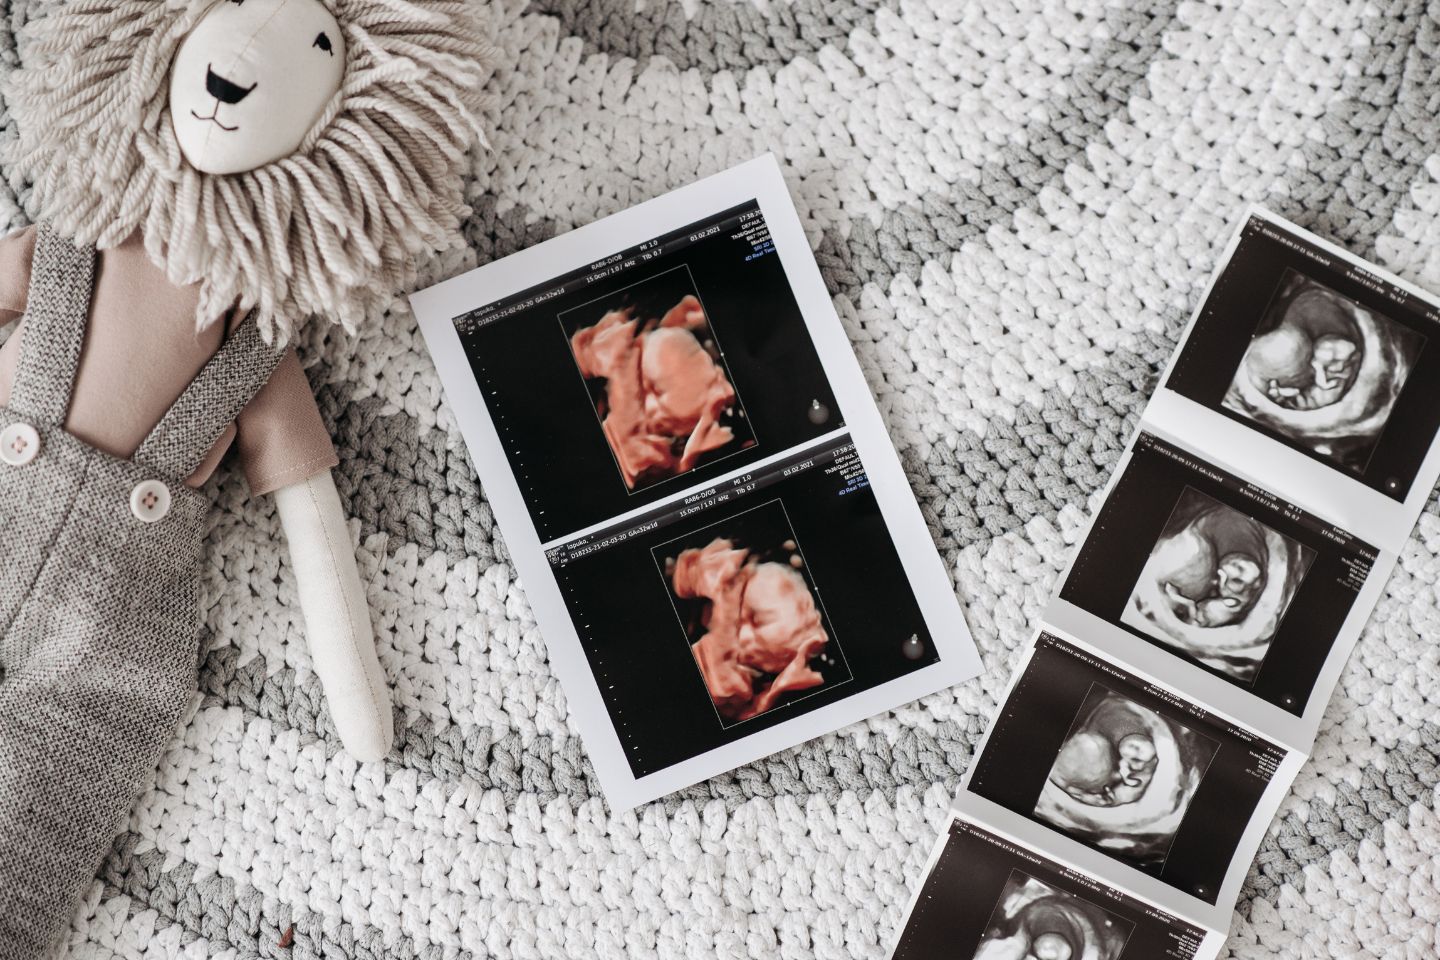

Das erste Mal die kleinen Hände des ungeborenen Kindes sehen, zum ersten Mal den Herzschlag hören, zu Hause dann das kleine Ultraschallbild an den Kühlschrank pinnen: Das sind Momente, die werdende Eltern wohl niemals vergessen. Seit den späten 1970er Jahren gibt es die Möglichkeit, ungeborene Babys via Ultraschall zu sehen und zu untersuchen. Als Teil der Vorsorge gehören drei große Termine während der Schwangerschaft dazu: Ein Termin pro Trimester. Die Kosten dafür übernimmt die Krankenkasse. Sollte es im Laufe der Schwangerschaft medizinische Gründe geben, weitere Ultraschall-Untersuchungen vorzunehmen, beispielsweise bei einer Risikoschwangerschaft, trägt die Krankenkasse auch diese Kosten.

Der erste Ultraschall ist meist besonders aufregend. Er findet in der Regel ab der 9. SSW statt. Hier lässt sich erkennen, ob sich der Embryo erfolgreich in der Fruchthöhle eingenistet hat. Dabei wird bei diesem Termin der Ultraschall vaginal durchgeführt, denn so lässt sich das Baby besser erkennen. Der Arzt oder die Ärztin kann jetzt auch benennen, in welcher Schwangerschaftswoche du dich befindest. Sprich: Bei diesem Ultraschall wird der genaue Geburtstermin errechnet. Zudem könnt ihr auf dem Monitor den Herzschlag zum ersten Mal wahrnehmen. Sicher festgestellt werden kann auch, ob es sich um eine Mehrlingsschwangerschaft handelt. Das Geschlecht des Babys erfahrt ihr bei diesem Termin allerdings noch nicht. Dafür ist es zu früh.

Jetzt lässt sich euer Baby schon richtig gut erkennen. Bei diesem Termin werden Bauchumfang, Kopfumfang sowie die Länge des Oberschenkelknochens gemessen und deine Ärztin oder dein Arzt kann die altersgerechte Entwicklung bestätigen. Zudem wird die Lage der Plazenta überprüft, während ihr auf dem Ultraschall die Bewegungen eures ungeborenen Kindes verfolgen könnt. Übrigens: Jetzt ist auch der Zeitpunkt, bei dem festgestellt werden kann, welches Geschlecht euer Baby hat. Ihr müsst vorab dem Arzt oder der Ärztin Bescheid geben, wenn ihr es nicht wissen wollt.

Dies ist der letzte große Ultraschall während der Schwagerschaft. Euer Ungeborenes wird noch einmal ausgemessen. Kindslage wie auch Lage der Plazenta werden überprüft. Beides ist wichtig für eure Geburtsplanung und den Ablauf. Doch keine Sorge: Sollte euer Kleines bei diesem Termin noch nicht mit dem Köpfchen nach unten liegen, müsst ihr euch nicht stressen. Viele Babys drehen sich meist erst gegen Ende der Schwangerschaft, manchmal auch erst kurz vor der Geburt. Einige Ärzt:innen haben übrigens für diesen Termin ein 3 D-Ultraschallgerät, das es euch ermöglicht, euer Wunder in all seiner Pracht und mit vielen Details zu bewundern.